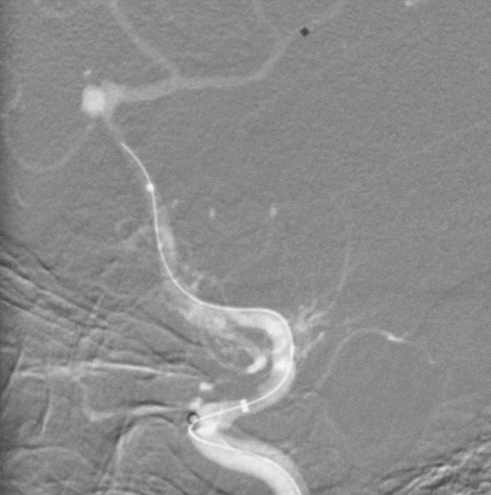

Tubridge Plus Case 3